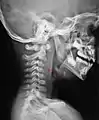

Un abcès rétropharyngien Un abcès rétropharyngien